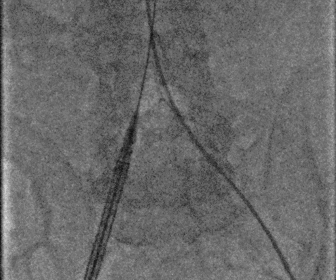

图片

18f鞘芯预扩张

球囊预扩

无鞘法上输送器

定位胶囊腔

瓣膜释放完毕

股动脉术后造影